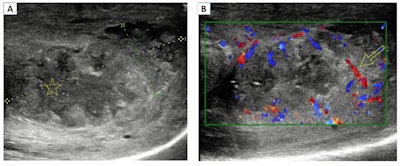

Abscess. B-mode ultrasound image (A) shows a heterogeneous collection with a central hypoechoic area and detritus inside the lesion (star). Color Doppler (B) shows an increased vascularity in the peripheral soft tissues (arrow).

A penile abscess typically requires therapeutic drainage. On ultrasound, it's visualized as a hypoechoic collection with debris and/or internal septa, without a Doppler signal inside the lesion. In some cases, it may contain gas bubbles, they added.